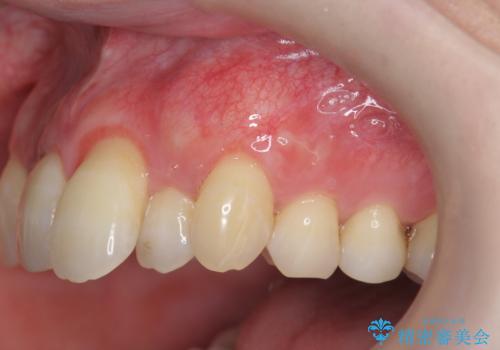

目立つ八重歯の歯ぐきのさがり 根面被覆による改善

良好な結果が得られ、大変満足いただくことができました。